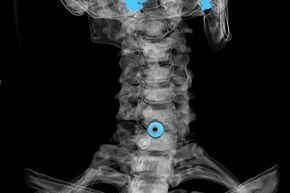

The diagnosis is established on the basis of characteristic symptoms, as well as with the help of:

- x-rays.The method is ineffective, especially in the last stages of development of osteochondrosis.

- MRI (magnetic resonance imaging) of the cervical vertebrae.A method that allows you to see bone structures, herniated intervertebral discs, their size and direction of development.

- Computed tomography.A less effective solution than MRI because the presence and size of the hernia is difficult to determine.